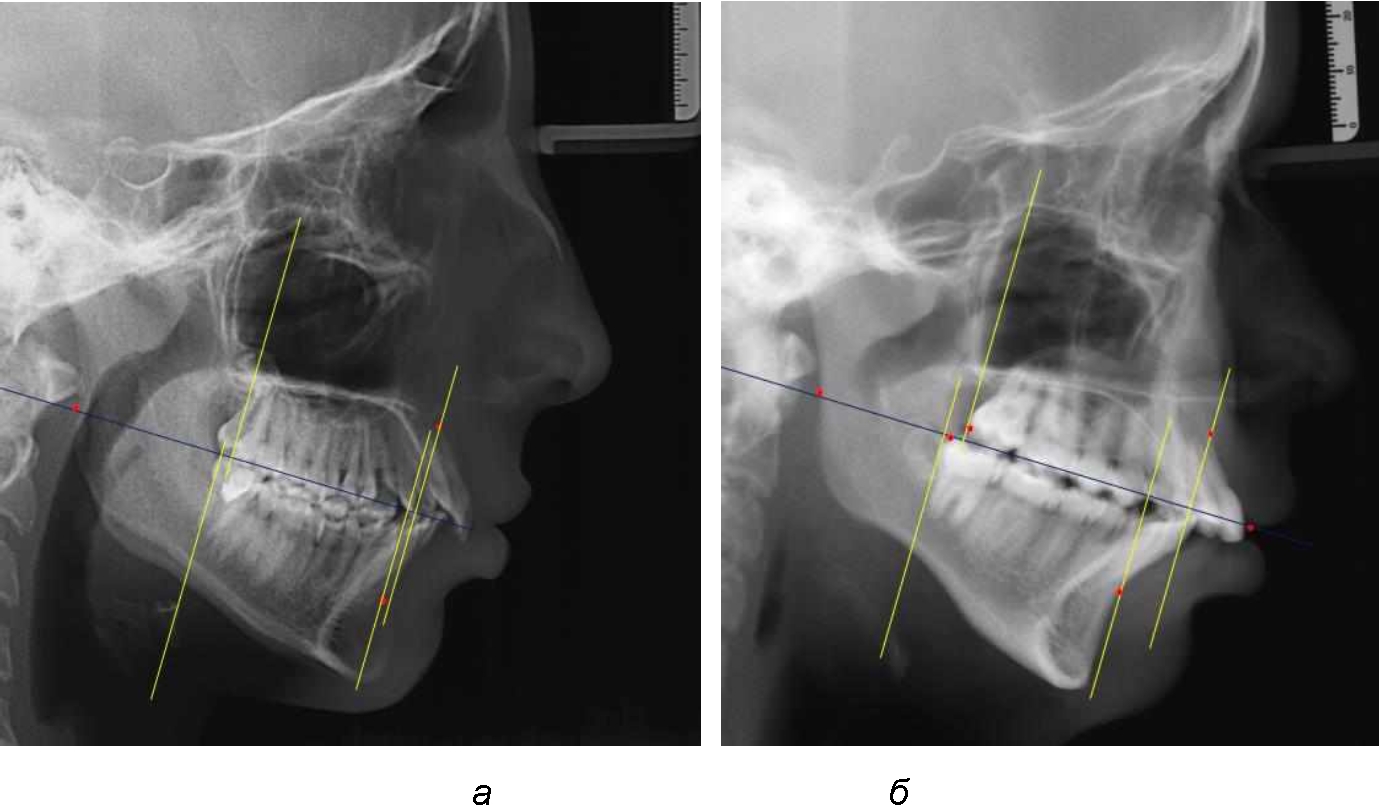

При анализе рентгенограмм, было отмечено, что на 26 снимках из 58 [(44,83 ± 6,53) %] отмечалась нормопозиция верхней челюсти. При этом средняя величина лицевого угла (ANSe) составила (85,04 ± 0,56)°, и пациенты были отнесены к 1-й группе 1-й подгруппе. Антепозиция верхней челюсти была отмечена на 20 те-лерентгенограммах [(34,483 ± 6,24) %], при этом величина лицевого угла составляла (89,12 ± 0,62)°. Ретропозиция была отмечена на 12 рентгенограммах [(20,69 ± 5,32) %], а средняя величина лицевого угла составляла (80,21 ± 0,48)°.

При всех вариантах положения верхней челюсти, было отмечено, что альвеолярно-денталь-ные размеры верхних зубо-челюстных дуг были близки по значению к аналогичным размерам нижней челюсти и разница в размерах не превышала 1,0–1,5 мм, а средняя величина различия показателей составляла (1,07 ± 0,54) мм.

Расстояние от конструируемой точки окклюзионной плоскости на ветви челюсти («rmРOcP») до апикальных точек Downs на обеих челюстях также коррелировало между собой, и средняя величина различия показателей составляла (1,23 ± 0,69) мм. Проекция нижней апикальной точки на окклюзионную линию, как правило, располагалась несколько кпереди проекции верхней апикальной точки, на величину около 1 мм, что соответствовало оптимальным данным Wits-анализа.

Аналогичное расстояние было отмечено и при расположении дистальных окклюзионных точек верхней и нижней челюсти (рис. 2).

Рис. 2. Положение апикальных точек и челюстей при нормопозиции (а), антепозиции (б) и ретропозиции (в) верхней челюсти